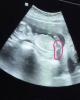

Девочки на сроке 19 недель какова вероятность ошибки в определении пола ?

От узиста зависит) если хороший специалист и аппарат 0 вероятность

С девочкой могут ошибиться, с мальчиком вряд ли

Если узист не слепой, то очень маленькая.